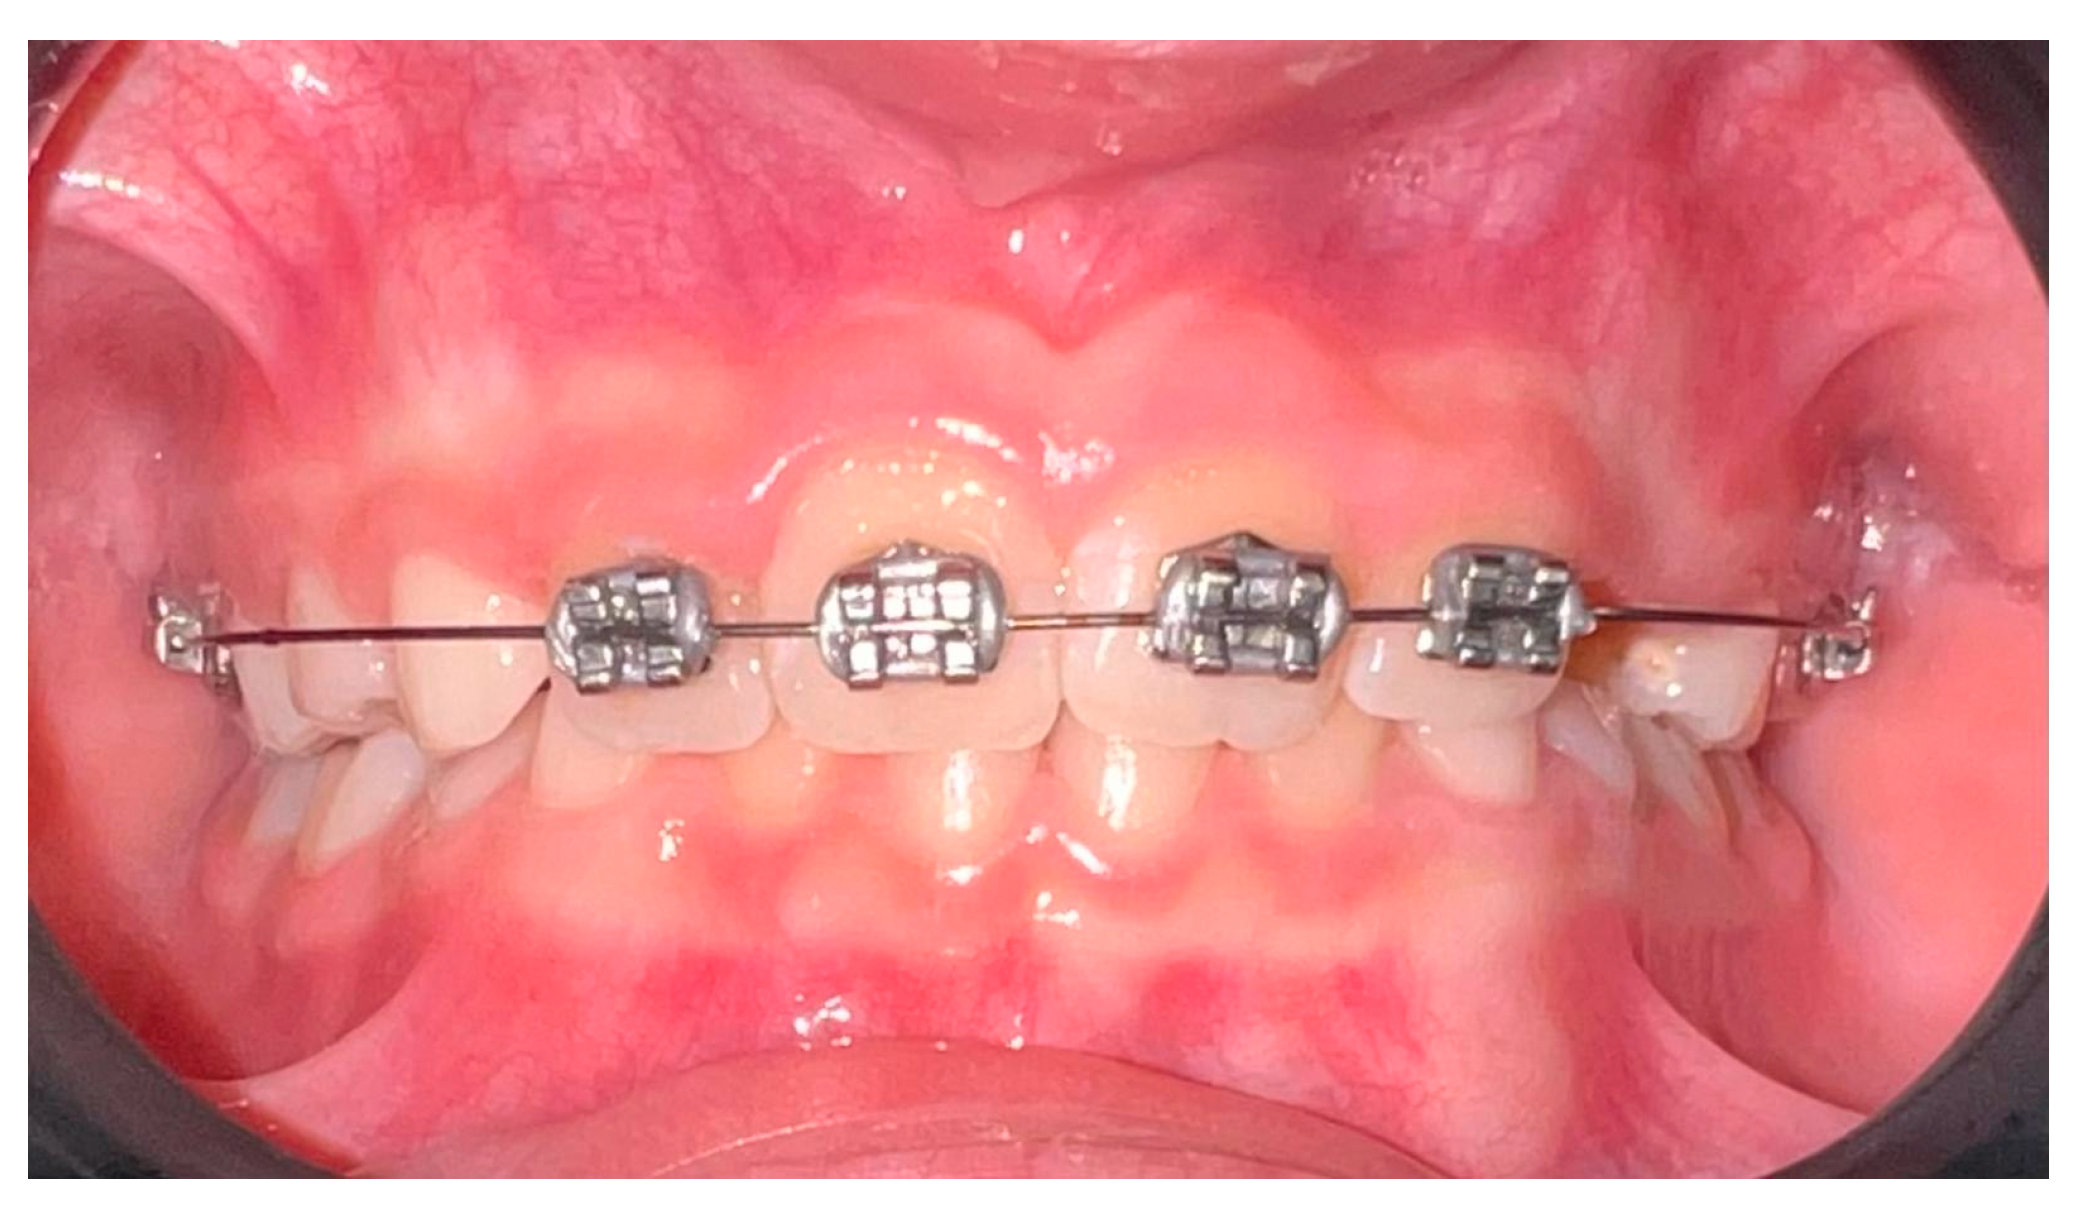

- Sockalingam, S.N.M.P.; Zakaria, A.S.I.; Khan, K.A.M.; Azmi, F.M.; Noor, N.M. Simple Orthodontic Correction of Rotated Malpositioned Teeth Using Sectional Wire and 2 × 4 Orthodontic Appliances in Mixed-Dentition: A Report of Two Cases. Case Rep. Dent. 2020, 2020, 6972196. [Google Scholar] [CrossRef]

| Da Silva, V. et al., 2023 [86] | Randomized clinical trial | 32 children (7–11 years old) | Compare efficacy and efficiency of clear aligners vs. 2 × 4 appliances in regard to mixed dentition | Digital dental models and 3D software were used. Patients were randomized into clear aligner or 2 × 4 fixed-appliance groups and treated for ~8 months. | Both methods showed similar efficacy; appliance choice can be based on clinician and family preference. |